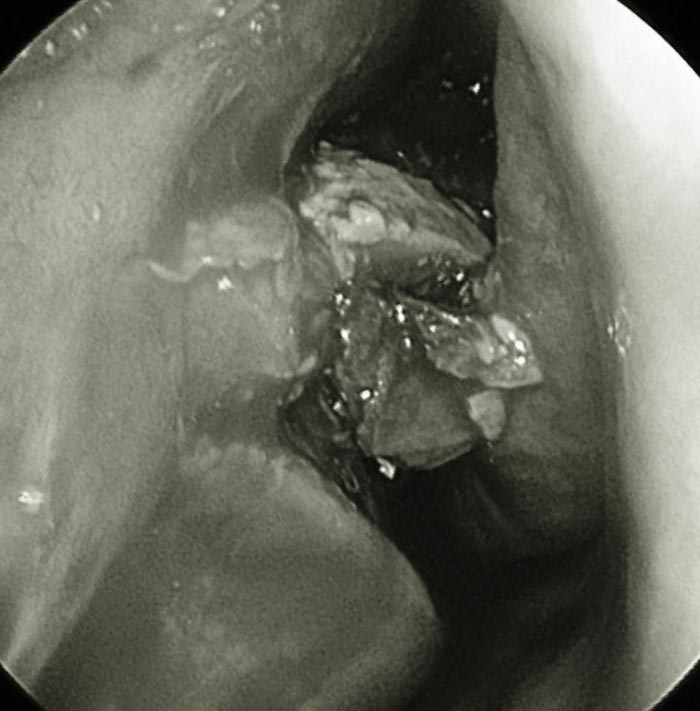

ดร.เฉิน เผยว่า หลังจากตรวจในเบื้องต้นเขาคาดว่าอาการของคนไข้น่าจะไม่ใช่แค่ไซนัสอักเสบเฉียบพลันแบบธรรมดา จึงได้ทำการตรวจซีทีสแกน จนได้พบว่า โพรงอากาศข้างจมูก หรือไซนัสฝั่งขวาของเธอถูกอุดตันด้วย ก้อนเชื้อราขนาดใหญ่ จึงวินิจฉัยว่า คนไข้หญิงรายนี้เป็น "ไซนัสอักเสบจากเชื้อรา" ต้องรักษาด้วยการผ่าตัด โดยแพทย์ได้นำก้อนเสมหะที่รวมอยู่กับเชื้อราออกจากโพรงจมูกของคนไข้อย่างระมัดระวัง จนสามารถนำออกมาได้ทั้งหมด ซึ่งพบว่ามีจำนวนมากอย่างน่าตกใจ

ภาพจาก เฟซบุ๊ก 耳鼻喉科 陳世璽醫師